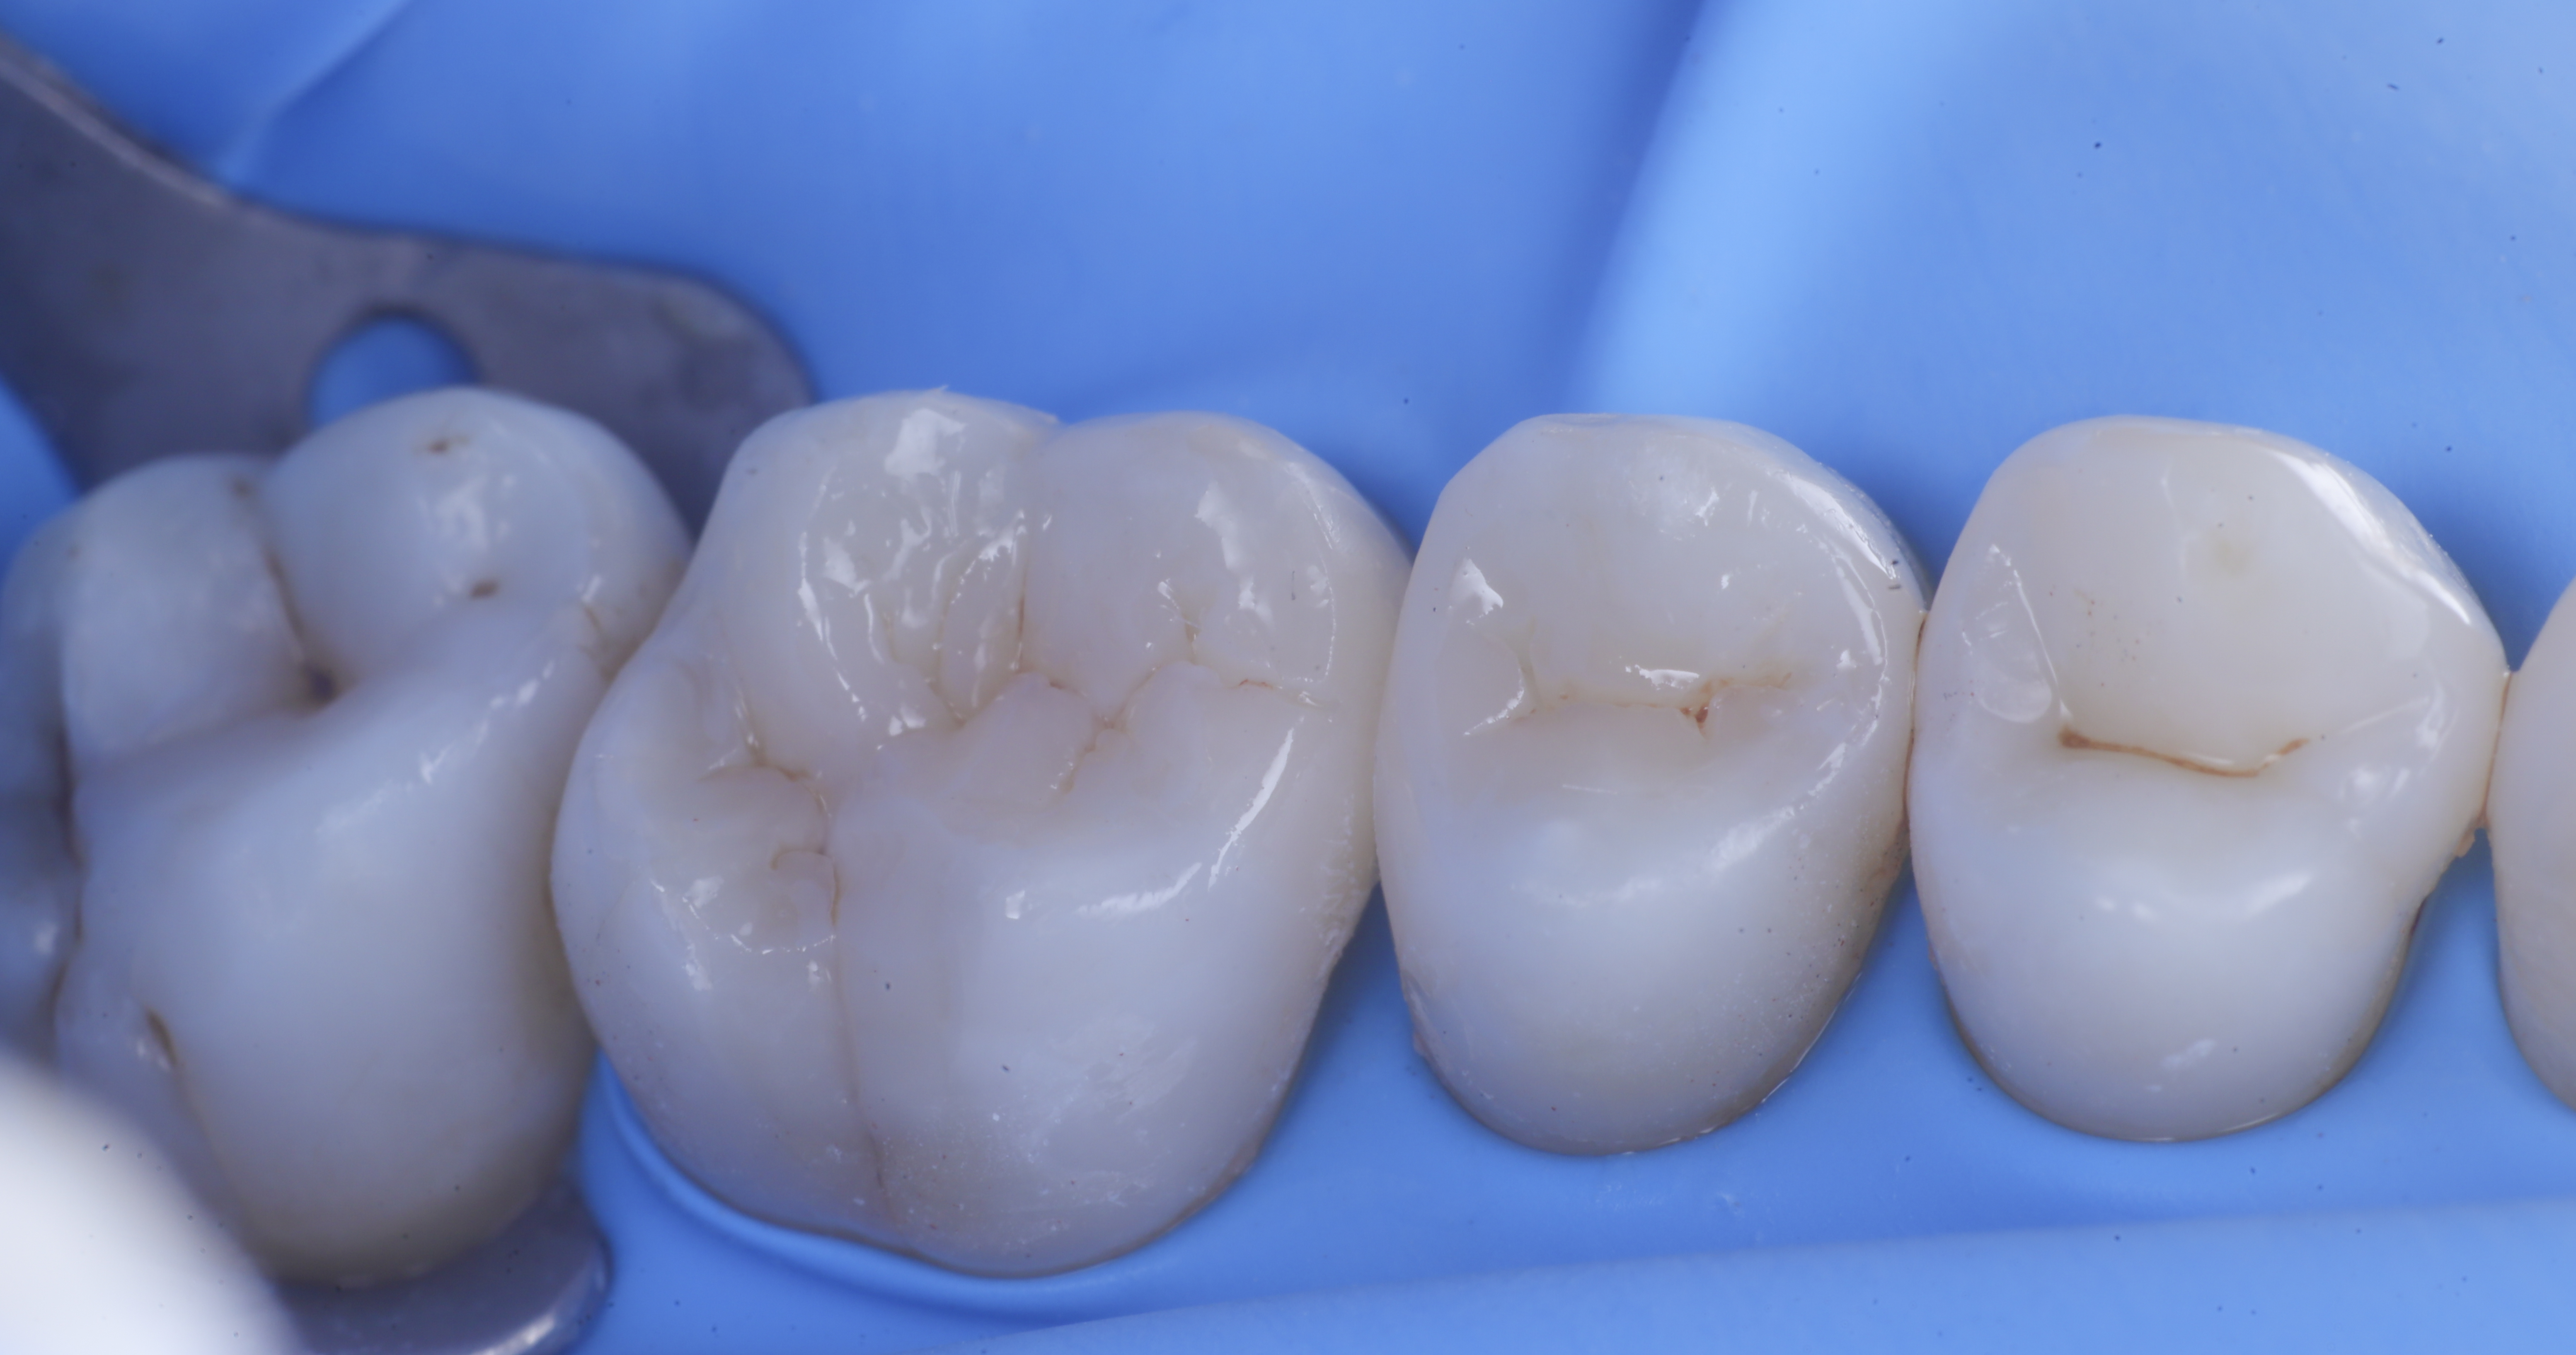

foto 6 Aspetto occlusale delle pareti interprossimali appena create

foto 7 Aspetto vestibolare delle pareti interprossimali appena create

foto 11 Restauri ultimati sotto controllo occlusale